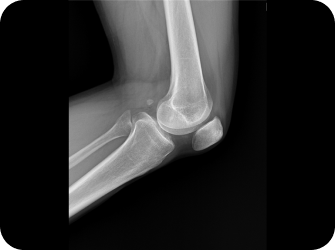

이제는 하세요!

엑스레이 검사

CT 검사

MRI 검사

초음파 검사